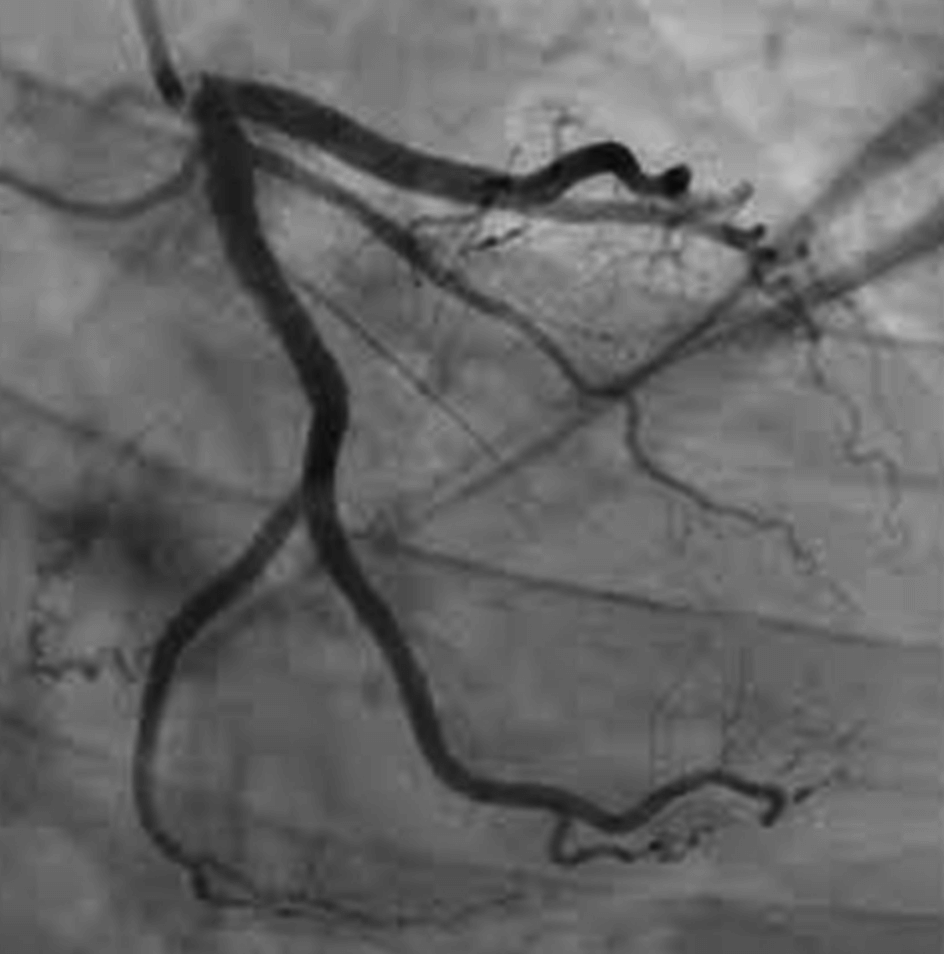

관상동맥 조영술은 X선 영상을 사용하여 심장의 혈관을 자세히 볼수 있는 기술입니다. 일반적으로 심장으로 가는 혈류에 제한이 있는지 확인하기 위해 수행되며 이를 확인하기 위해 특수 염료인 조영제와 X-레이를 사용하는 절차입니다.

심장 상태를 진단하는데 도움을 주는 관상동맥 조영술은 가장 일반적인 심장도관 시술이며, X선기계는 조영술로 지나가는 혈관의 이미지를 촬영하여 혈관을 살표봅니다. 이때 필요한 경우 의사는 관상동맥 조영술중에 막힌 심장 동맥을 혈관성형술로 시술 할수도 있습니다.